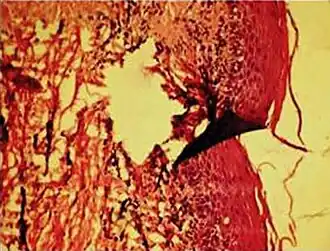

Formalin pigment artifacts

Air bubble entrapment artifact in a shoulder joint biopsy